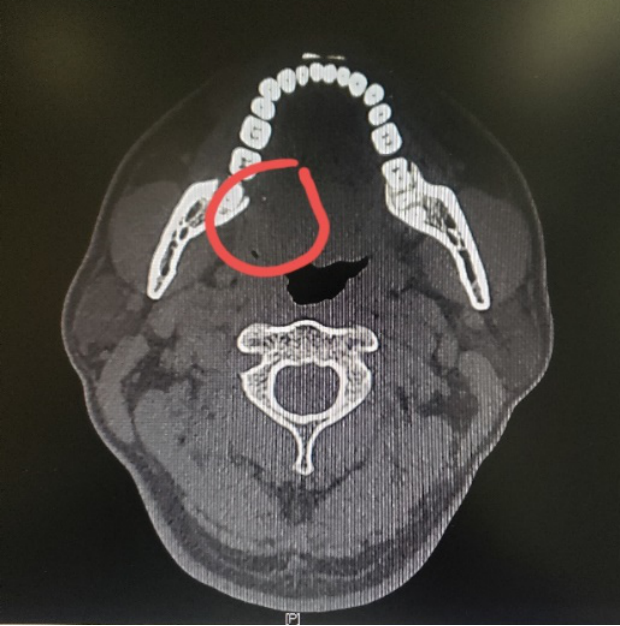

图一:病人的术前CT

图二:病人的术前MRI

图三:病人的术前MRI

图四:病人的术前MRI

那么这个异物包裹性脓肿里面到底是什么呢?我猜测要不是鸡骨,要不就是鱼刺,但鸡骨的话体积比较大,在CT上一般能看得出来,而且这么大的鸡骨插进舌头,病人的症状会非常明显,不会等到几个月后才来就诊。而鱼骨一般是很纤细的,在CT上是看不出来的,不过我们仔细看影像的话,还是可以在切面上发现小的阻射影的。